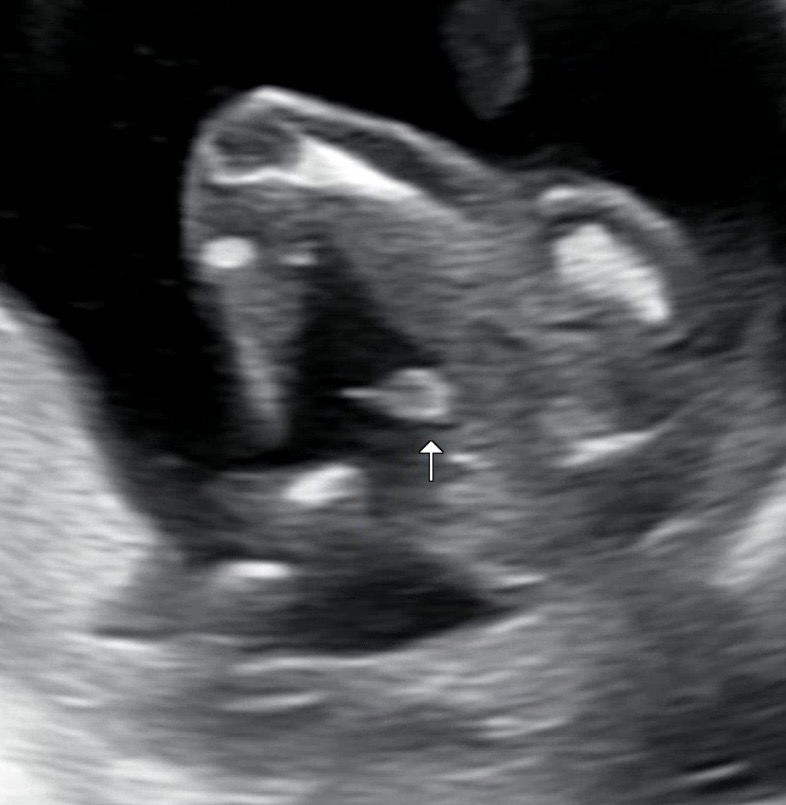

16주 0일 성별!

너무 확실한 아들...! 동생이 몇일 전 딸을 낳아서 같이 예쁘게 공동육아하면서 키우고싶어서 딸을 원하긴 했으나 건강한 아들이더라구요..ㅎㅎ 남자 형제가 없어서요ㅠㅠ 아들의 장점을 알려주세요!

저도 아들인데 너무너무 존재가 확실하더라고요:) 곧휴🥰🌶️ 축하드려요❤️❤️

곧휴가 너무 뚜렷해서 놀랬어요😖 축하드려용🎂